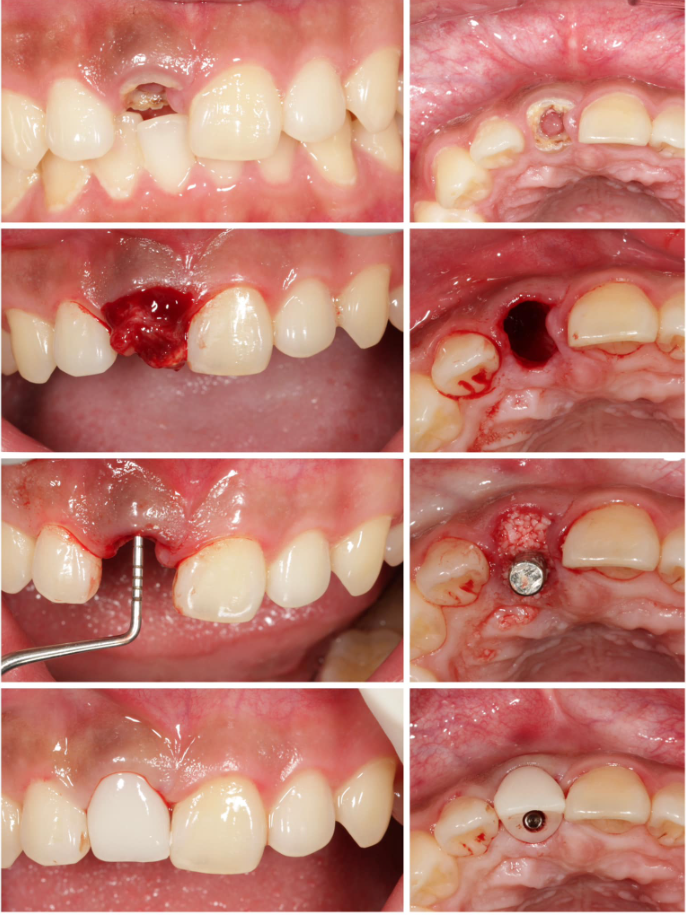

Ngoài ra, tại nha khoa Lạc Việt Intech, đội ngũ bác sĩ và cơ sở vật chất đảm bảo đủ điều kiện để thực hiện các phương pháp cấy ghép, thủ thuật phức tạp như cấy ghép tức thì, giải pháp phục hình cá nhân hóa DCT, ghép lợi...

Một ca phục hình cấy ghép Implant tức thì kết hợp ghép xương, được thực hiện đúng quy trình và đảm bảo an toàn tại Nha khoa Lạc Việt Intech